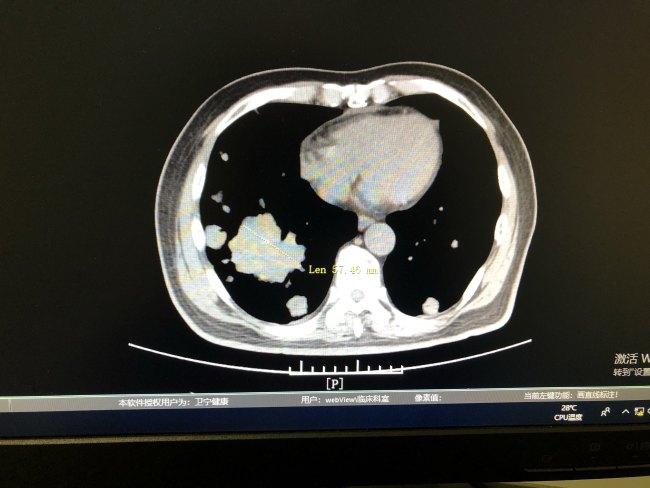

在丈夫和婆婆的陪伴下,吳芬前往浙江省腫瘤醫院求診,外科醫師診斷後表示,她的情況已不能接受手術,建議她轉到胸部內科。

吳芬本以為自己命在旦夕,但內科醫師以基因檢測結合標靶藥物治療方法,令她順利抗癌至今。她回憶起這8年的抗癌經歷:「要是沒有這麼多好心人,想盡辦法救我的命,我真的沒想到自己能活到現在。」